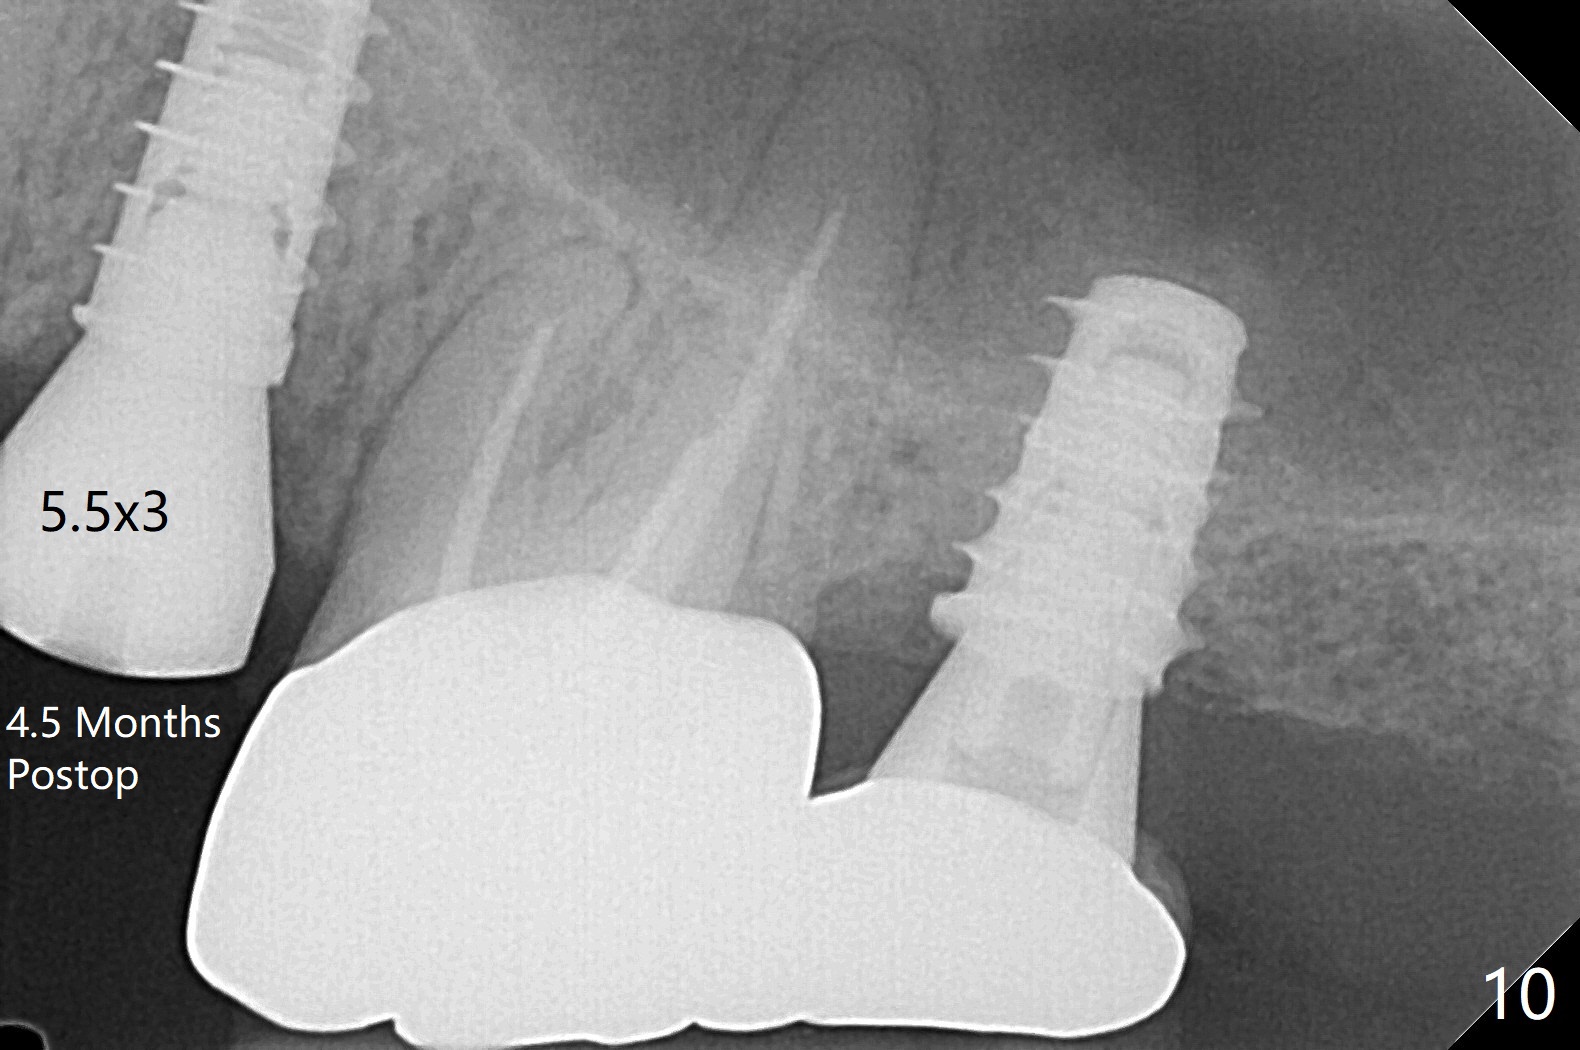

The patient with the anterior cross bite at the left lateral and canine and incipient Class V caries returns to clinic for #13 residual root extraction (Fig.1,2). There is no quality root structure (Fig.2) or space (Fig.3) for socket sheath. Two amalgam carriers of Vanilla is inserted and pushed by the 4x11 mm dummy implant for sinus lift (Fig.4 *). When the same sized final implant (4x11 mm) is placed, a 5.5 mm bone profile drill is used to trim the proximal crests (Fig.5 * sticky bone packed in the buccal and palatal gaps). In fact the implant turns when a 4.5x4(3) mm pair abutment is tightened. The implant is backed up; with a healing screw, sticky bone is placed (Fig.6 *) and then covered with a piece of PRF and a part of GEM cap. The wound is sutured with 4-0 PGA; periodontal dressing is applied. The implant is somewhat over-seated without the bone graft covering the apical end of the implant (Fig.7, as compared to Fig.4). A 4.5 mm implant should be placed. The GEM Cap appears to be absent 9 days postop, while the periodontal dressing dislodged in 1 week (Fig.8). It appears that the existing abutment at #15 is incompletely seated (Fig.3, 5.5x4(2) mm). After use of 5.5 and 6.0 mm bone profile drills, a 5x4(3) mm abutment is placed with 35 Ncm torque. In fact the bone graft coronal to the implant remains (Fig.9 *) in spite of apparent loss of the overlying PRF and GEM cap (Fig.8). After use of a 4.6 mm profile drill, a 5.5x3 mm healing abutment is placed 4.5 months postop (Fig.10). Without a provisional at #13 for ~ 4 months, there is a gap between crowns at #14 and 15 (not shown due to angulation). Impression is taken for #13 crown fabrication 5.5 months postop and for #15 crown repair (addition of porcelain for the mesial contact, Fig.11). It appears critical for a provisional to maintain the position of the neighboring tooth.